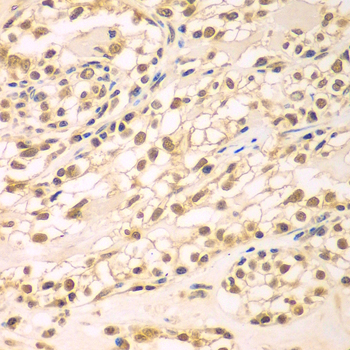

Immunohistochemistry of paraffin-embedded human oophoroma using TBL1XR1 antibody at dilution of 1:100 (x400 lens).

Immunohistochemistry of paraffin-embedded human brain cancer using TBL1XR1 antibody at dilution of 1:100 (x400 lens).

Immunohistochemistry of paraffin-embedded human kidney using TBL1XR1 antibody at dilution of 1:100 (x400 lens).